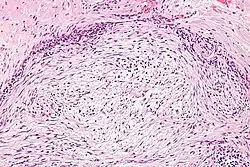

| Micrograph of nodular fasciitis showing the haphazard arrangement of cells (tissue culture-like pattern). H&E stain. | |

The microscopic histopathology of hematoxylin and eosin stained nodular fasciitis tumors consists of spindle-shaped myofibroblastic cells.[8] These cells are in a myxoid or a collagenous (high content of collagen fibers) tissue background. The neoplastic myofibroblasts are arranged in whorls and/or short bundles. These cells may show high rates of replicating as judged by their mitotic index, but these mitoses are normal in appearance. The tumor tissues often contain red blood cells, lymphocytes, and giant osteoclast-like cells, and may contain sites of bone-like tissue.[10] NF is sometimes classified into three subtypes based on its predominant histopathological pattern: myxoid or reactive (type I), cellular (type II), and fibrous (type III).[4] These patterns appear related to the duration of the lesion, with the myxoid variant tending to have the shortest duration and the cellular and fibrous variants tending to have progressively longer durations.[14] Immunohistochemical analyses indicate that the cells in NF usually express smooth muscle actin, muscle specific actin, and vimentin proteins but generally do not express CD34, S-100 protein, desmin, trypsin, factor VIII, F4/80, or HLA-DR1 proteins.[10] Uncommonly, the cells in NF tumors express the CD68 (a histiocyte-specific marker) protein.[4]